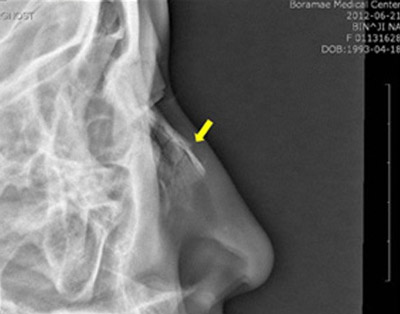

- Рентгенографія кісток носа. Проводиться в прямій і бічній проекціях. Призначається для підтвердження перелому, визначення його виду і локалізації, оцінки напрямку й виразності зміщення фрагментів.

перелом носа на рентгенівському знімку

- Найбільш інформативними діагностичними методами є рентгенографічний і томографический. Оглядова рентгенограма дозволяє визначити вид перелому і поставити остаточний діагноз.